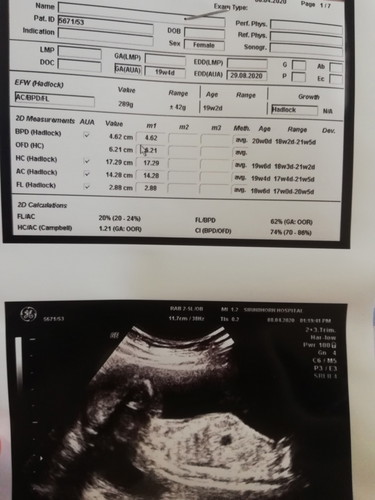

สับสนมากค่ะ วันนี้ไปซาวคุณหมอไม่ได้ชี้ให้ดูเพศลูก แต่บอกว่าได้ลูกชายนะ กลับบ้านมาเลยดูในใบซาว ช่องเพศเขียนว่า female เป็นผู้หญิง ยึดตามที่คุณหมอบอกใช่ไหมคะ.

บอกเพศของแม่จ้า.. ประวัติของคนที่ไปตรวจจ้า

Female มันขึ้นช่องประวัติopd. ของแม่นะคะ

เพศหญิงคือเพศของแม่ที่ไปตรวจค่า

ที่พิมพ์ช่องเพศนั้นคือเพศแม่จ้า

ช่องที่ใส่ Female คือเพศของแม่ค่ะ 😊

นั้นมันเพศแม่ค่ะ ในใบซาวด์นะ